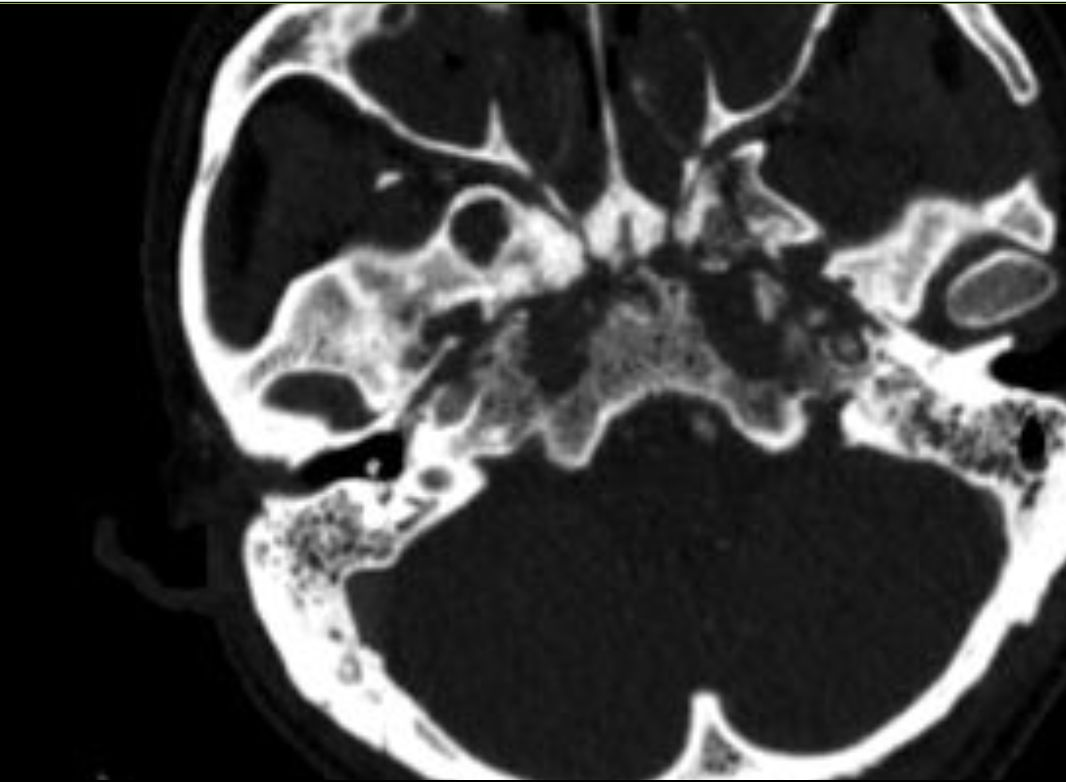

转诊至环湖医院之前,患者因放射性鼻咽颅底坏死导致了致命的并发症——左侧颈内动脉破裂出血,同时右侧颈内动脉也存在重度狭窄。已在外院接受了左侧颈内动脉的覆膜支架植入止血,在ICU抢救治疗生命体征稍平稳,但状况依然危急,依靠芬太尼镇痛,身体极度消瘦,重度贫血,低蛋白血症,坏死病灶没有清除随时有再次严重出血风险。根据文献和临床病例判断,如果不接受病变切除和颅底修复治疗,绝大多数患者可能因颅底大血管破裂出血面临生命危险。

外院CTA检查:左侧颈内动脉破裂孔段假性动脉瘤形成,右侧颈内动脉起始部重度狭窄